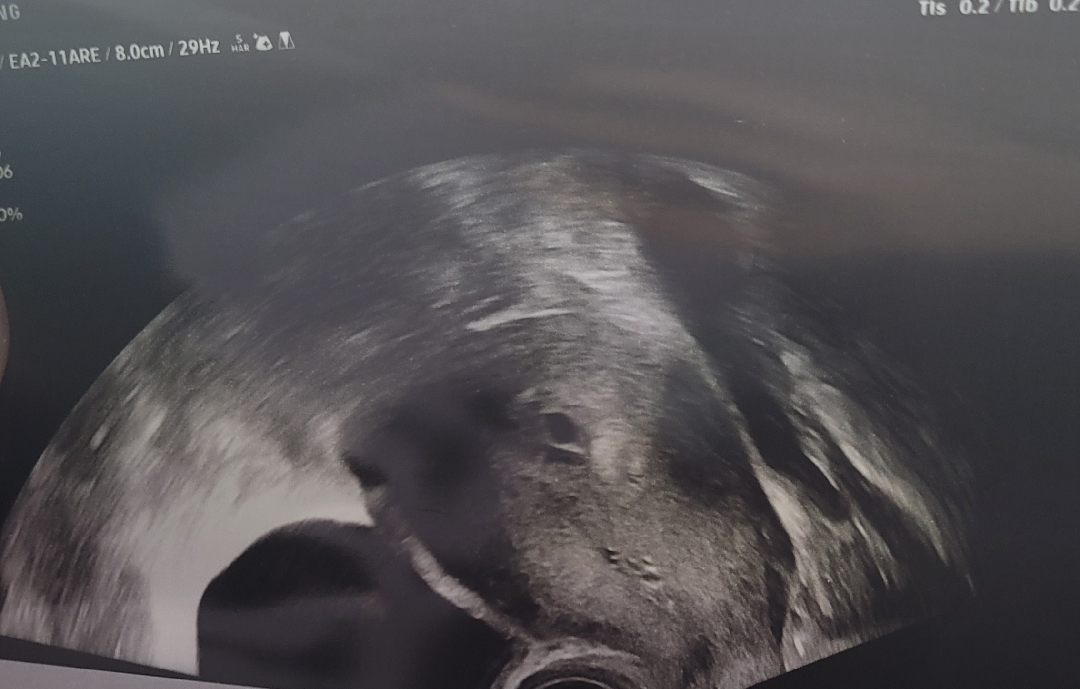

오늘 막생기준으로 6주 4일 차입니다 배란일 1월 17~19일로 추정 오늘 초음파보자고하셔서 보고왔는데 의사선생님이 크기도 주수에 비해서 많이 작은편이고 피고임인지 아기집인지 아직 확실하지않다고 하시네요 크기가 5주 0일차 사이즈라고... 산모수첩이랑 임신확인서는 떼주셧어요! 피고임이라기엔 동그래서 아기집이라고 믿고있는데 비슷한 경험하신분 조언부탁드립니다!